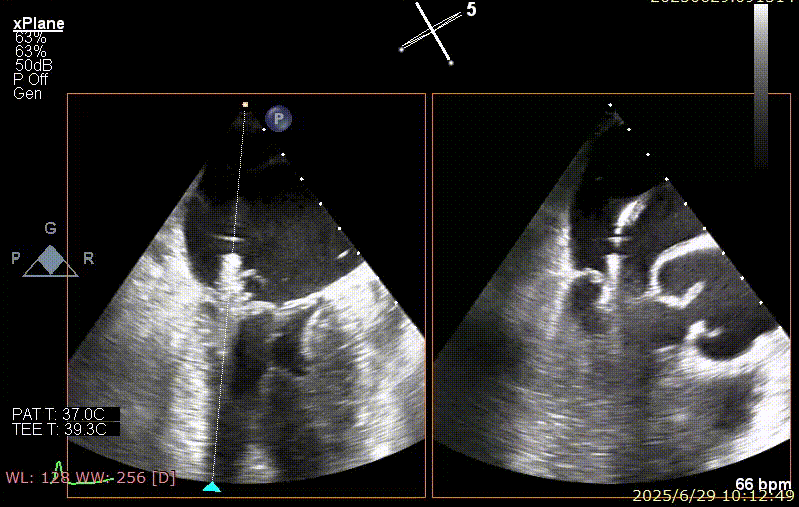

2025 年 6 月 29 日,经过对术前超声和 CT 影像进行深入分析,团队制定了周密手术计划。在麻醉手术中心副护士长刘菊梅的充分术前准备和中国医学科学院阜外医院欧阳文斌教授的指导下,凭借团队的紧密协作和娴熟操作,单纯利用超声影像精确引导,通过导引导管系统经右胸、右房,穿房间隔,建立到达左房通路;经该通路将两枚二尖瓣钳夹成功植入二尖瓣病变部位进行夹持,夹合器位于 3 区及部分 2 区,固定好,运动协调,瓣叶启闭灵活,瓣口轻度反流,二尖瓣平均跨瓣压差 2 mmHg。手术圆满完成。

手术步骤

器械植入后二尖瓣 AP 径约 35 mm,CC 径约 39 mm;夹合器固定好、组织桥稳定,前瓣夹闭后瓣叶长度 25 mm,后瓣夹闭后瓣叶长度 7 mm;二尖瓣开放好,瓣口呈大小双孔,二尖瓣瓣口面积约 2.8 cm²,平均压差 1 mmHg,关闭可,二尖瓣反流明显减轻(从术前反流 4+显著改善至 1+),手术全程无需体外循环支持,无需输血,无需射线全超声引导。患者术后第二日回普通病房,患者恢复良好,术后第五日即出院。